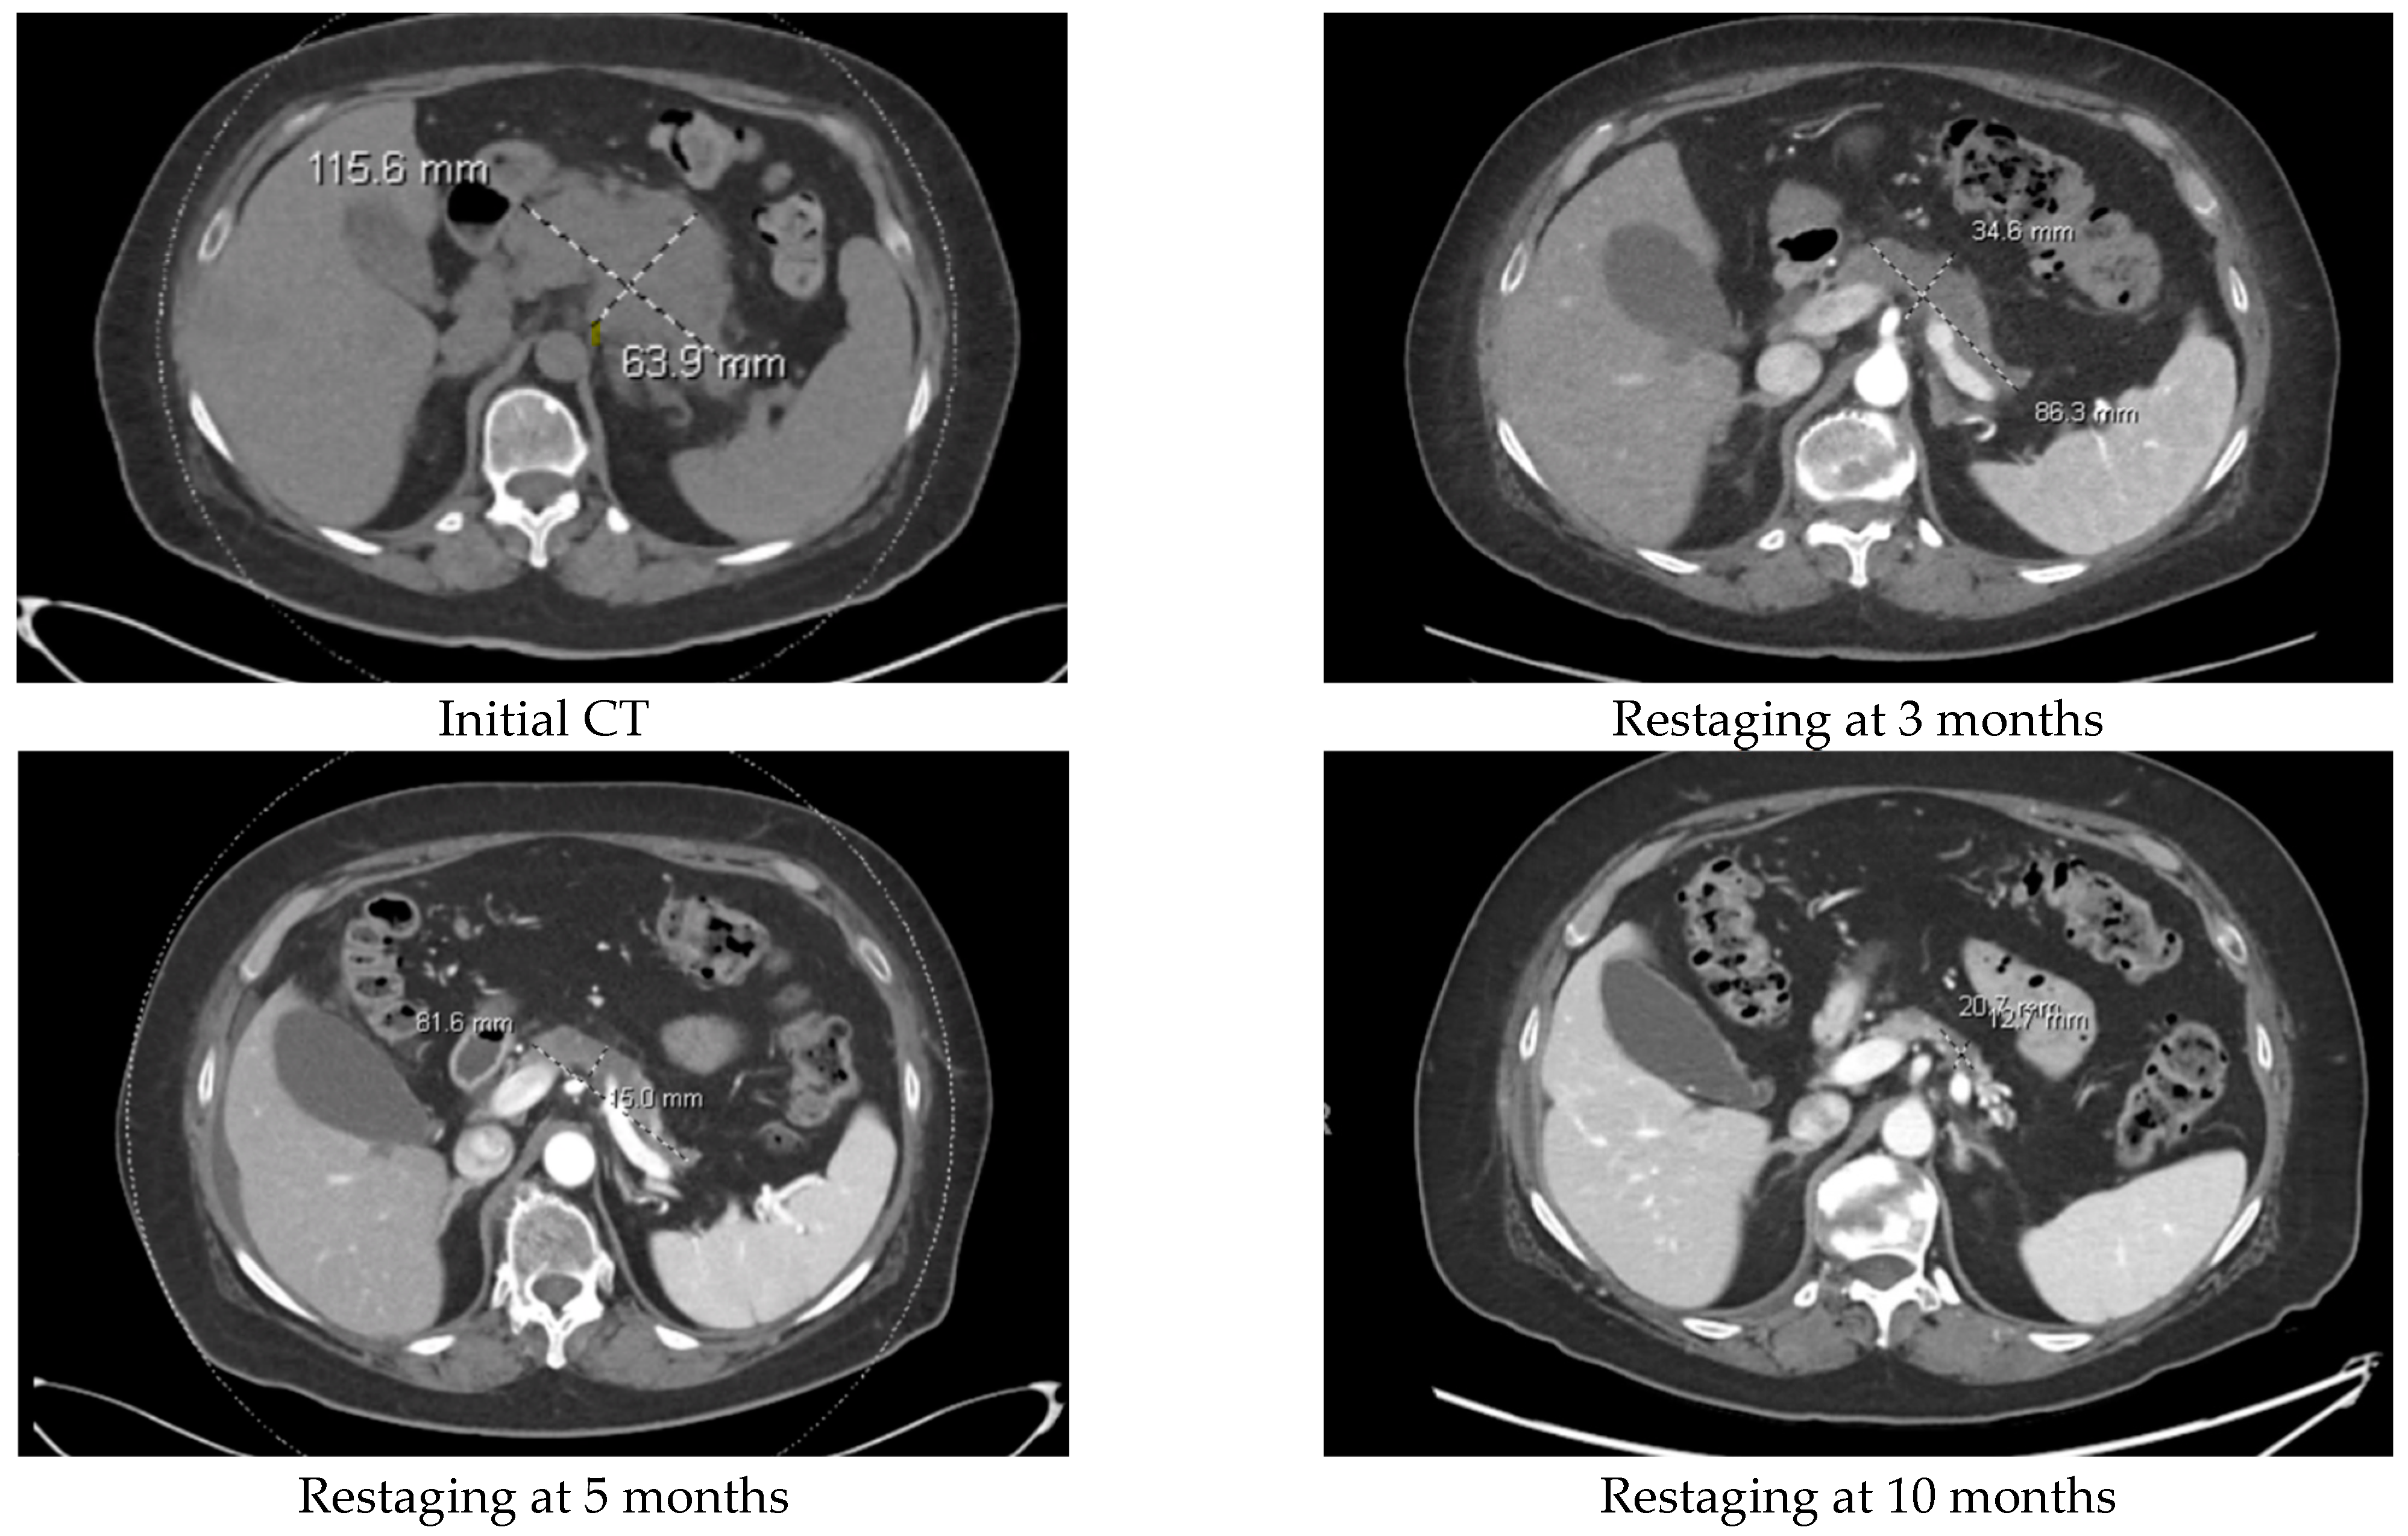

| 58/F | Folfirinox 1 mo switch when RET-1 gene fusion identified. | Selpercatinib. Continuing to show PR. | 26 | |